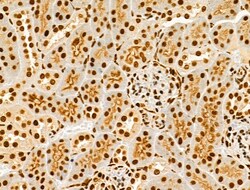

Invitrogen™ Phospho-AKT1 (Ser124) Polyclonal Antibody

Antibody detects endogenous levels of AKT1 only when phosphorylated at Ser124.

| Immunohistochemistry (Paraffin), Western Blot, Immunocytochemistry | |

| Human, Mouse, Rat | |